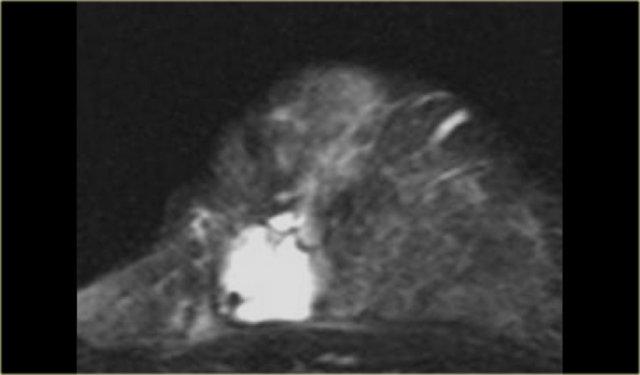

Ung thư tiểu thùy xâm lấn

Ung thư tiểu thùy xâm lấn là một trong những loại ung thư không phải lúc nào cũng

biểu hiện ngấm thuốc nhiều trên MRI vú, điều này có thể gây khó khăn cho chẩn đoán.

Tuy nhiên, trong hai trường hợp này, đây không phải là vấn đề.

Hình ảnh ngoài cùng bên trái là ung thư tiểu thùy xâm lấn lan tỏa.

Bên phải là ảnh MIP cho thấy một vùng ngấm thuốc bất thường rộng lớn, được xác định là ung thư tiểu thùy xâm lấn lan tỏa.